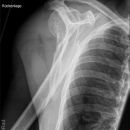

Dislozierte subcapitale Fraktur mit Tbc majus